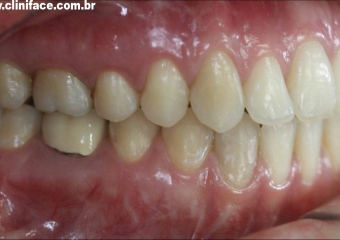

Imagem mordida perfil inicial